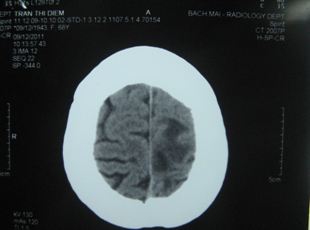

Chụp CT sọ não (9/12): Có u não ở vùng đỉnh trái, kích thước khoảng 1,8 cm, có phù não xung quanh khối u.

Hình 1: Hình ảnh chụp CT sọ não có u não ở vùng đỉnh trái, kích thước khoảng 1,8 cm, có phù não xung quanh khối u